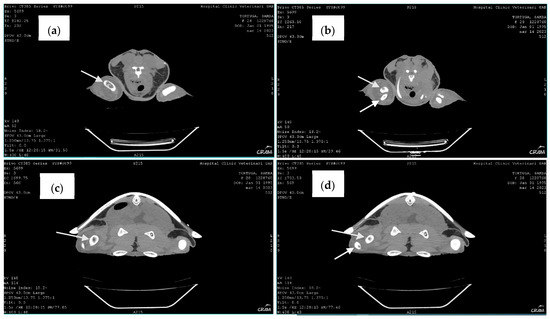

Therefore, to better visualize the lesions, computed tomography (CT) of the whole body, in soft tissue and bone algorithm, with 1.25 mm thick sections, without administration of intravenous iodinated contrast, was performed. CT confirmed the lytic lesions observed in radiography on the distal right humerus, proximal right radius and ulna, distal right femur, and proximal right tibia and fibula. When clinical signs appeared, blood culture at 24–26 °C with antibiogram was performed, revealing a positive result.

Late-stage lesions after five months of rehabilitation were characterized by sclerosis and remodeling of the lesion borders (Figure 7). Lesions occurring within the bone shaft typically remain asymptomatic. However, those adjacent to the joint surface, known as juxta-articular lesions, may advance to structural deterioration of the joint surface, leading to symptoms such as pain and restricted movement. CT revealed additional lytic bone lesions of the left ischium, ileum, and pubis; right ischium; left humerus head; and confirmed the lytic lesions observed via radiography (Figure 8). Throughout the treatment period, the animal continued to have a healthy appetite and was bright and alert according to Manire et al. 2017, Sea Turtle Health & Rehabilitation [22]. Blood samples were taken once a month to evaluate hematological and biochemical values, and all the parameters were in range according to plasma biochemical and hematological baseline values in loggerhead sea turtles from the Mediterranean Sea proposed by Basile et al. (2011) [19].

Figure 8. Computed tomography. Note bone lysis on the distal end of the right humerus (arrow) (a), the proximal end of the right radius and ulna (arrows) (b), and the proximal end of the right tibia and fibula (arrows) (c,d).